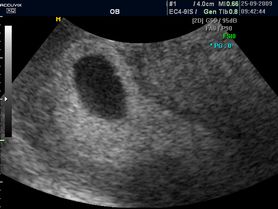

Pierwszy trymestr ciąży - badanie USG, ciąża tydzień po tygodniu

Płód w 10 tygodniu ciąży (zdjęcia)

Płód w 9 tygodniu ciąży (zdjęcia)

Płód w 8 tygodniu ciąży (zdjęcia)

Płód w 6 tygodniu ciąży

Płód w 5 tygodniu ciąży

Płód w 4 tygodniu ciąży